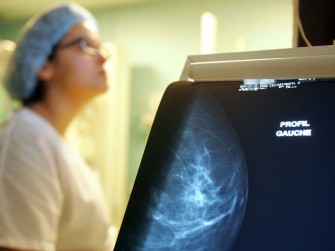

Journée Thématique sur l’Imagerie de la Femme - Octobre Rose- 31 Octobre 2025

La Société Algérienne de Radiologie et d’Imagerie Médicale - SARIM, en partenariat avec ASTARTÉ - Association Transméditerranéenne : Femme et Cancer du Sein, a le plaisir de vous inviter à participer...